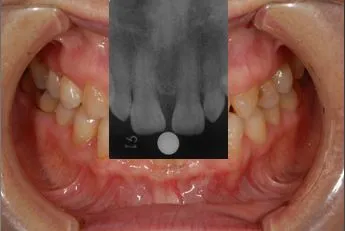

CASE1 60代女性 ダイレクトボンディングによる修復治療

初診

歯石除去で来院されました。

除去後、話を聞くと上顎の前歯の歯と歯の間が離れていることが

以前より気になっていると仰られ、治療計画を立案。

レントゲン写真を撮影。

口腔内写真の撮影

残っている歯の問題点などを解析

顔全体・口元の写真を解析

前方・口元

側方・口元

口腔内の分析・治療計画

さまざまな方向性から、歯のバランスや問題点を解析。

治療計画の立案を行います。